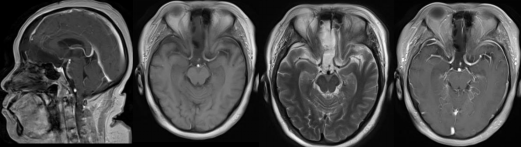

术前影像资料

肿瘤位于鞍窝及鞍上区,肿瘤大小约3*2.5*3厘米,肿瘤呈囊实性,囊液为灰黑色粘稠液体,实质部分呈灰黄色,质地较韧,部分钙化,囊壁与垂体柄、下丘脑和双侧视神经、视交叉、颈内动脉粘连。其中与垂体柄粘连紧密。